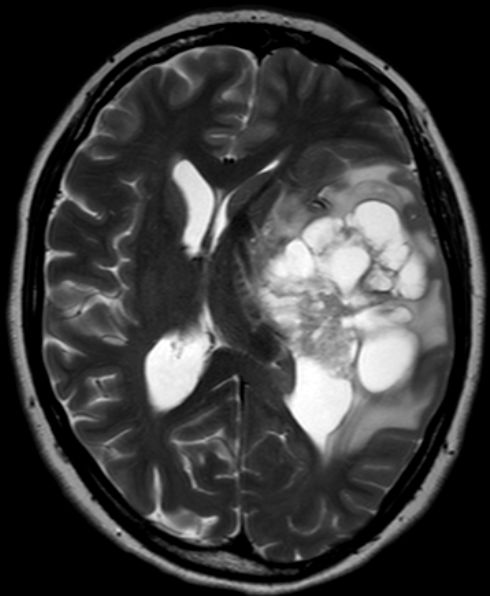

78-jährige Frau mit einen Grand-Mal-Anfall.

GBM der Insel rechts![]() MRT, TR 10.000/TE 140 |

Ausdehnung auf den Temporallappen rechts![]() | |||